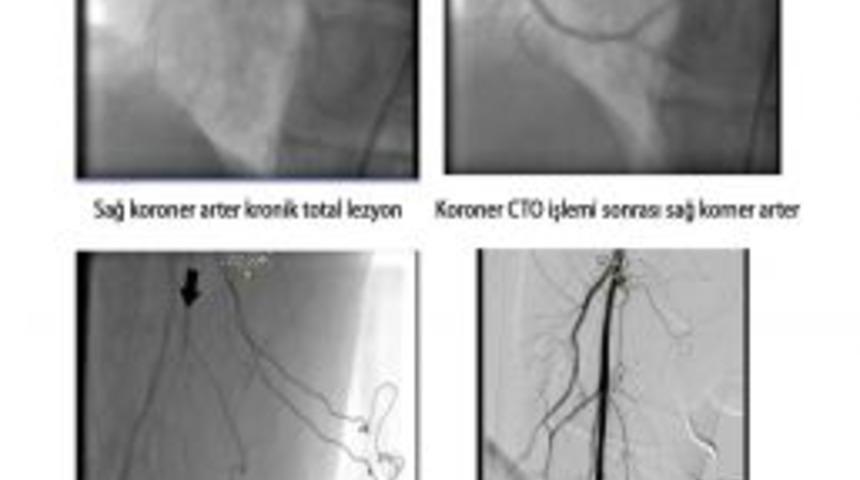

Medical Park Samsun Hastanesi Kardiyoloji Uzmanı Dr. Emre Aksakal, koroner damar veya periferik damarların kronik tam tıkanıklıklarında şimdiye kadar ameliyatın tek çözüm olarak sunulduğunu ama artık kronik total oklüzyonlu (CTO) hastalarda ameliyatın tek çözüm olmaktan çıktığını söyledi.

Uzm. Dr. Emre Aksakal, "Tüm kalp damar tıkanıklıklarının yüzde 20-30'unu CTO'lu hastalar oluşturmaktadır. Bir damara CTO denebilmesi için 3 aydan uzun süredir tam tıkalı olmalıdır. Tam tıkalı olan damarlar ya kendi üzerinden yardımcı damarlarla ya da diğer damarlar üzerinden dolum göstermektedir. Tıkalı bölge kollaterallerle beslenmesine rağmen hastalarda göğüs ağrısı ve nefes darlığı gibi şikayetler olur ve zamanla kalp yetmezliği ve ani ölümler gelişebilir" dedi.

Dr. Aksakal, Medical Park Samsun Hastanesi gibi sadece koroner girişimsel uygulamaların yoğun uygulandığı merkezlerde yapılabilecek bu uygulamalarla hem bacak hem de kalp damarlarında ameliyat dışında çözümü olmayan veya ameliyat sonrası tekrar tam tıkanan damarların açılmasında CTO uygulamalarının bir umut olduğunu vurguladı.

CTO uygulamalarının anjiyografi işlemleri gibi yapılmakta olduğunu söyleyen Uzm. Dr. Emre Aksakal, "Özel kataterler ve total oklüzyon telleri ile antegrad veya retrograd yolla total oklüzyondan geçilerek damar lümeni açılmakta ve PTCA ve stent uygulamaları yapılarak damar açıklığı sağlanmaktadır. CTO uygulamaları sayesinde, açılmaz denen damarların açılması ile hasta, ameliyatsız sağlığına kavuşmaktadır. Bu uygulamalar ameliyat gereksinimini yüzde 30 azaltmaktadır" diye konuştu.